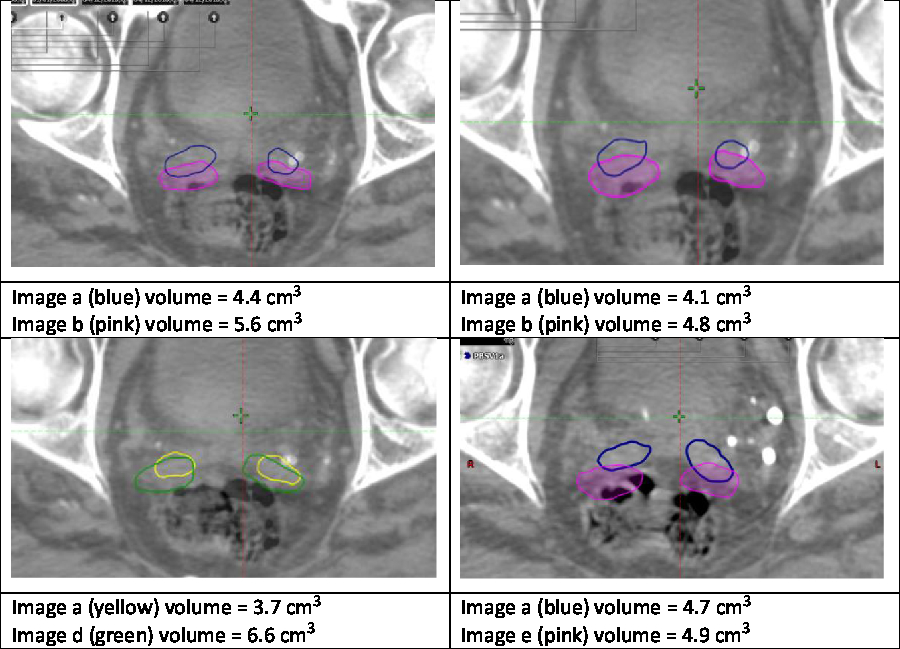

Noteworthy examples from these data are depicted in Figure 1, with overlaid contours highlighting volumetric and positional variation in Case One. In particular, a large volume variation can be seen in the bottom left image. In contrast, the bottom right image demonstrates an identical volume but clear positional variation. Variability in the mean outlined volumes is depicted graphically for each case and user in Figure 2. The data anonymisation process removed date stamps from the datasets, so the chronological order of fractions is unknown.

Figure 1. Example variation in Case One.